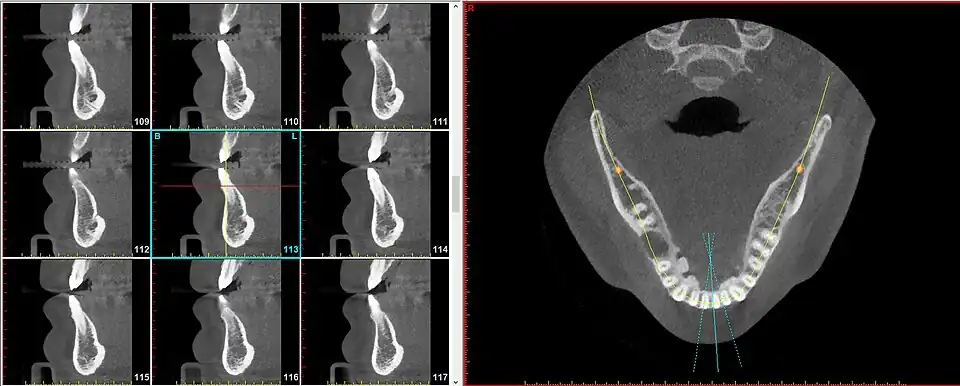

A radial plane is an anatomical plane that is used to describe a virtual slice along a radius of a somewhat cylindrical shaped body part.[1] The radial planes need not be perfectly drawn to overlap on an exact intersection point, particularly when the body part being sectioned is not a perfect cylinder, such as in the case of the maxilla and mandible.

The radial plane can be useful because certain anatomical elements repeat in a circumferential manner (such as around the curvature of the dental arch (i.e. the jaw) and to speak of these entities using parallel planes becomes cumbersome and inaccurate.

For instance, the segment of bone on the outer circumference of each individual tooth is referred to as the facial plate of bone. Because the facial plate of bone is anterior to the incisors (in the front of the mouth) but lateral to the premolars and molars (in the back of the mouth), to visualize the facial plate of bone on various teeth will require sagittal slices for the former but coronal slices for the latter. To achieve greater uniformity and diminished confusion, simply speaking of radial slices provides a satisfactory solution for all teeth in both (upper and lower) arches.

Previous to the advent of this terminology, this plane was referred to as the axial plane relative to the body of the jawbone. It was believed that the jawbone was straightened out as though it were a straight tube, and then transverse (axial) sections were made of that tube.